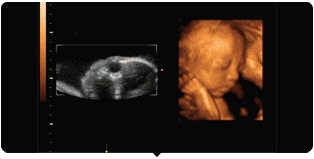

整个孕期中,B超都是一项很重要的检查

不仅因为它能监测宝宝的发育和健康状况

更因为这项检查颇具神秘色彩

能透过你的肚皮

看到宝宝的模样和动作

1.四维彩超的检查目的

通过四维超声检查,能够准确反映出胎儿生长发育情况,多角度、多方位进行胎儿异常评估。包括先天疾病。如胎儿唇腭裂、四肢发育畸形、脑膜膨出、脊柱裂、腹壁裂等先天畸形。